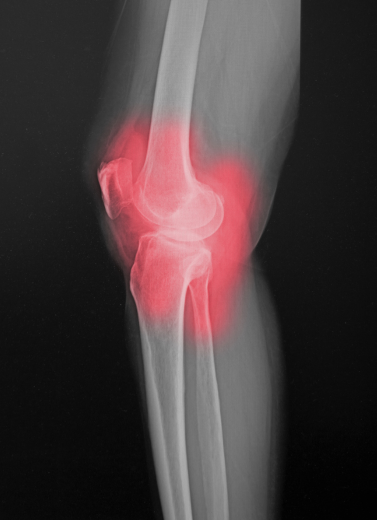

MIS-ZERO Total Knee Replacement

Partial Knee Replacement (Unicondylar TKR)

Osteoarthritis (Knee, Hip, Shoulder)

Rheumatoid Arthritis

Post-Traumatic Joint Damage